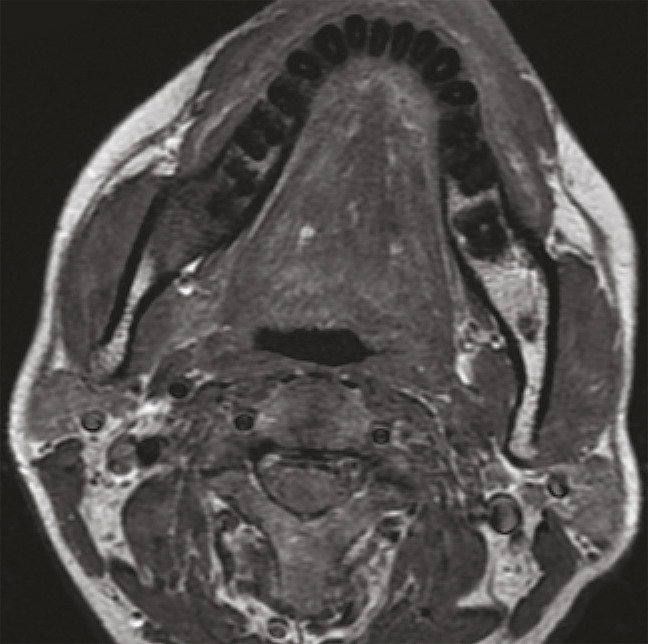

En TDM, au cours de l’acquisition en respiration douce, les sinus piriformes sont souvent fermés, et les trois parois (antérieure, latérale et postérieure) ne sont pas analysables de façon satisfaisante. Il est donc nécessaire de compléter l’examen par une hélice au cours de laquelle le patient réalise une manœuvre de Valsalva, ce qui dégage les reliefs anatomiques. La lésion apparaît développée aux dépens d’une ou plusieurs de ses parois (fig. 4), faisant plus ou moins saillie dans la lumière pharyngée, et/ou infiltrant les parties molles profondes tant latéralement que dans l’axe vertical (espaces graisseux parapharyngés, muscles laryngés, structure glottique, bouche de l’œsophage, base de la langue).